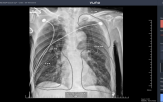

폐의 염증과 폐렴이 겹치며 1년 가까이 병원을 제집처럼 드나드는 고통의 시간을 보냈다. 간신히 기운을 차릴 무렵, 암은 다시 그를 찾아왔다. 1년 뒤 왼쪽 폐에서 새로운 결절이 발견되었고 2023년에는 결국 오른쪽 폐에서 암이 재발하며 '비소세포폐암 3기' 확진을 받았다. 반복되는 항암과 방사선 치료, 그리고...

CT 의료영상에서 폐결절 악성 종양 여부를 진단 보조하는 소프트웨어’로, 저선량 흉부 CT 기반 폐암 조기 발견을 지원하는 AI 솔루션이다. 코어라인소프트는 해당 제품을 중심으로 국가 폐암검진, 공공의료원 디지털 전환 사업, 정부 R&D 연계 과제 등 다수의 B2G 프로젝트에 참여하며 레퍼런스를 축적해왔다. 특히 최근...

의료기관에 AI 폐결절 검출 SW 첫 공급 (서울=연합뉴스) 최현석 기자 = 코어라인소프트[384470]는 호주 니피언 영상의학센터(Nepean Diagnostics)에 인공지능(AI) 폐결절·폐기종·관상동맥석회화 검출 SW '에이뷰 엘씨에스 플러스(AVIEW LCS Plus)'를 공급한다고 2일 밝혔다. 에이뷰 엘씨에스 플러스는 저선량...